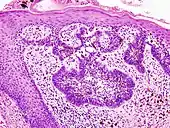

Main types of staining seen on H&E stain.

H&E is the combination of two histological stains: hematoxylin and eosin. The hematoxylin stains cell nuclei a purplish blue, and eosin stains the extracellular matrix and cytoplasm pink, with other structures taking on different shades, hues, and combinations of these colors.[5][6] Hence a pathologist can easily differentiate between the nuclear and cytoplasmic parts of a cell, and additionally, the overall patterns of coloration from the stain show the general layout and distribution of cells and provides a general overview of a tissue sample's structure.[7] Thus, pattern recognition, both by expert humans themselves and by software that aids those experts (in digital pathology), provides histologic information.

Hematoxylin principally colors the nuclei of cells blue or dark-purple,[6][15][14] along with a few other tissues, such as keratohyalin granules and calcified material. Eosin stains the cytoplasm and some other structures including extracellular matrix such as collagen[5][7][14] in up to five shades of pink.[8] The eosinophilic (substances that are stained by eosin)[5] structures are generally composed of intracellular or extracellular proteins. The Lewy bodies and Mallory bodies are examples of eosinophilic structures. Most of the cytoplasm is eosinophilic and is rendered pink.[10][15] Red blood cells are stained intensely red.